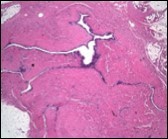

Morphological analysis preponderantly demonstrates a solitary, uni-locular or multi-locular cyst of Mullerian origin with an epithelial lining recapitulating the epithelium of fallopian tube.

Cutaneous ciliated cyst is layered with a singular layer of ciliated epithelial cells which are chiefly constituted by cuboidal to columnar epithelium, traversed by partially configured fibrous tissue septa with an admixture of randomly dispersed, intraluminal papillary projections akin to those cogitated in the fallopian tube. Superimposed epithelium is inundated with well vascularized, parallel bundles of collagen although smooth muscle is absent 7, 8.

Figure 5.Cutaneous ciliated cyst with incomplete intervening septa and a lining of attenuated, ciliated epithelium along with supporting fibrous tissue (13).

Figure 6.Cutaneous ciliated cyst with a ciliated cuboidal lining, undulations within the cyst cavity and a wall comprised of fibro-connective tissue (14).